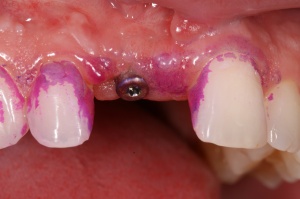

Ab dem Februar 2004 wurde der Patient zur Sicherung des Behandlungserfolges in das in der FU VIIa – Zahnmedizin seit 1996 praktizierte Recallsystem aufgenommen. Diese Erhaltungstherapie beinhaltet die bereits erwähnten Maßnahmen der Unterstützenden Parodontitistherapie (UPT). Aufgrund dienstlicher Erfordernisse (u. a. immer wieder Seefahrten des Patienten) konnte der zunächst geplante Abstand von vier Monaten nicht immer eingehalten werden. Ein Abstand von ca. sechs Monaten konnte jedoch trotz der teilweise schwierigen Rahmenbedingungen realisiert werden. Am Zahn 44 kam es im Jahr 2006 zu einem Rezidiv, sodass an diesem Zahn im September 2006 eine Lappenoperation durchgeführt wurde. Der intraoperativ vorgefundene tiefe cirkuläre vertikale Defekt führte zur Einschätzung einer langfristig fraglichen Prognose von 44. Im Zuge der weiteren Erhaltungstherapie zeigten sich bis auf 44 die parodontalen und periimplantären Gewebe völlig unauffällig: So betrugen die Sondiertiefen bei entzündungsfreien klinischen Verhältnissen durchweg zwei bis drei Millimeter. Auch radiologisch zeigten sich keine Auffälligkeiten. Es gab keine Progredienz der ehemaligen parodontalen Erkrankung, die Osseointegration der Implantate zeigte keine Veränderungen (s. Abb. 7). Erhöhte Sondiertiefen verblieben lediglich am Zahn 44. Nachdem sich trotz regelmäßiger Nachsorge an 44 keine Entzündungsfreiheit der marginalen Gingiva erzielen ließ und die Zahnlockerung von 44 zunehmend stärker wurde, erfolgte im Jahre 2010 die Entfernung des Zahnes und der Ersatz durch eine implantatgetragene Krone (s. Abb. 8). Die Erhaltungstherapie wurde fortgeführt, Behandlungsmaßnahmen über die Inhalte der UPT hinaus waren bis zur Entlassung des Soldaten im Jahre 2012 nicht erforderlich. Der Patient blieb jedoch auch nach der Entlassung aus dem aktiven Dienst Patient des Hauses, sodass die Erhaltungstherapie in der FU VIIa – Zahnmedizin fortgeführt werden konnte. Im April 2013 stellte sich der Patient mit Beschwerden am Zahn 45 vor, der Zahn wies zudem eine Lockerung des Grades II auf. Die durchgeführte Röntgendiagnostik (s. Abb. 9) zeigte eine Wurzelfraktur im apikalen Wurzeldrittel, ein Zahnerhalt von 45 war nicht möglich und der Zahn wurde noch in gleicher Sitzung entfernt. Zur Versorgung der Lücke wären verschiedene prothetische Lösungen möglich gewesen. Letztlich fiel die Entscheidung zugunsten eine Extensionsbrücke von regio 45 auf 48. So konnte die Implantatkrone 44 belassen und mit dem Lückenschluss mittels einer vergleichsweise einfachen und schnellen prothetischen Versorgung auch die Schaltlücke 46 geschlossen werden. Der Patient befindet sich nach wie vor in der FU VIIa in der Erhaltungstherapie, die Fotos zeigen den aktuellen klinischen Befund in der Aufsicht des Ober- und Unterkiefers (s. Abb. 10, 11).